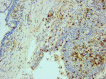

Otosclerosis is a bone condition affecting the stapes bone within the otic capsule, and its exact cause is still unknown. It is characterized by a lack of proper remodeling of newly formed vascular and woven bone, leading to the development of abnormal osteons and the formation of sclerotic bone. Bilateral otosclerosis is seen in 80% of patients and 60% of otosclerosis patients have a family history of the condition. The etiology of this disease is still unknown, there are lots of theories to explain it. The histopathological (HP) studies of otosclerosis showed that osteoblasts, osteoclasts, vascular proliferation, fibroblasts, and histiocytes were observed in the stapes footplate. The onset of the symptoms occurs by the early third decade of life, usually it doesn't start later. In otosclerosis, the energy exerted by sound at the level of the tympanic membrane is reduced in the inner ear due to the fixation and rigidity of the ossicular chain, leading to hearing loss, especially for low frequencies. The primary clinical symptom of otosclerosis is conductive hearing loss but it is important to note that sensorineural hearing loss and mixed hearing loss can also occur as secondary symptoms of the condition. Another symptom present in patients with otosclerosis is tinnitus. The paper carried out a retrospective study of 70 patients diagnosed with otosclerosis in the Department of Otorhinolaryngology of Emergency City Hospital, Timişoara, Romania, between January 2021 to December 2022. Tissue fragments were processed at Service of Pathology by standard Hematoxylin-Eosin staining. The HP diagnosis was completed using Masson's trichrome staining, Giemsa histochemical staining, and immunohistochemical (IHC) reactions with anti-cluster of differentiation (CD)20, anti-CD3, anti-CD4, anti-CD8, anti-CD34, and anti-CD31 antibodies. The microscopic examination showed a chronic diffuse inflammatory infiltrate that consisted predominantly of mature T-lymphocytes, immunohistochemically positive for CD3, CD4 and CD8. There were also present rare CD20-positive B-lymphocytes. Among the lymphocytes, relatively numerous mast cells were identified, highlighted histochemically by the Giemsa staining. They had numerous purple-violet intracytoplasmic granules. In the connective tissue support, a relatively rich vascular network was identified, consisting of hyperemic capillaries, highlighted immunohistochemically with anti-CD31 and anti-CD34 antibodies. Bone tissues trabeculae showed extensive areas of fibrosis. The collagen fibers were highlighted by Masson's trichrome staining, being stained in green, blue, or bluish green.